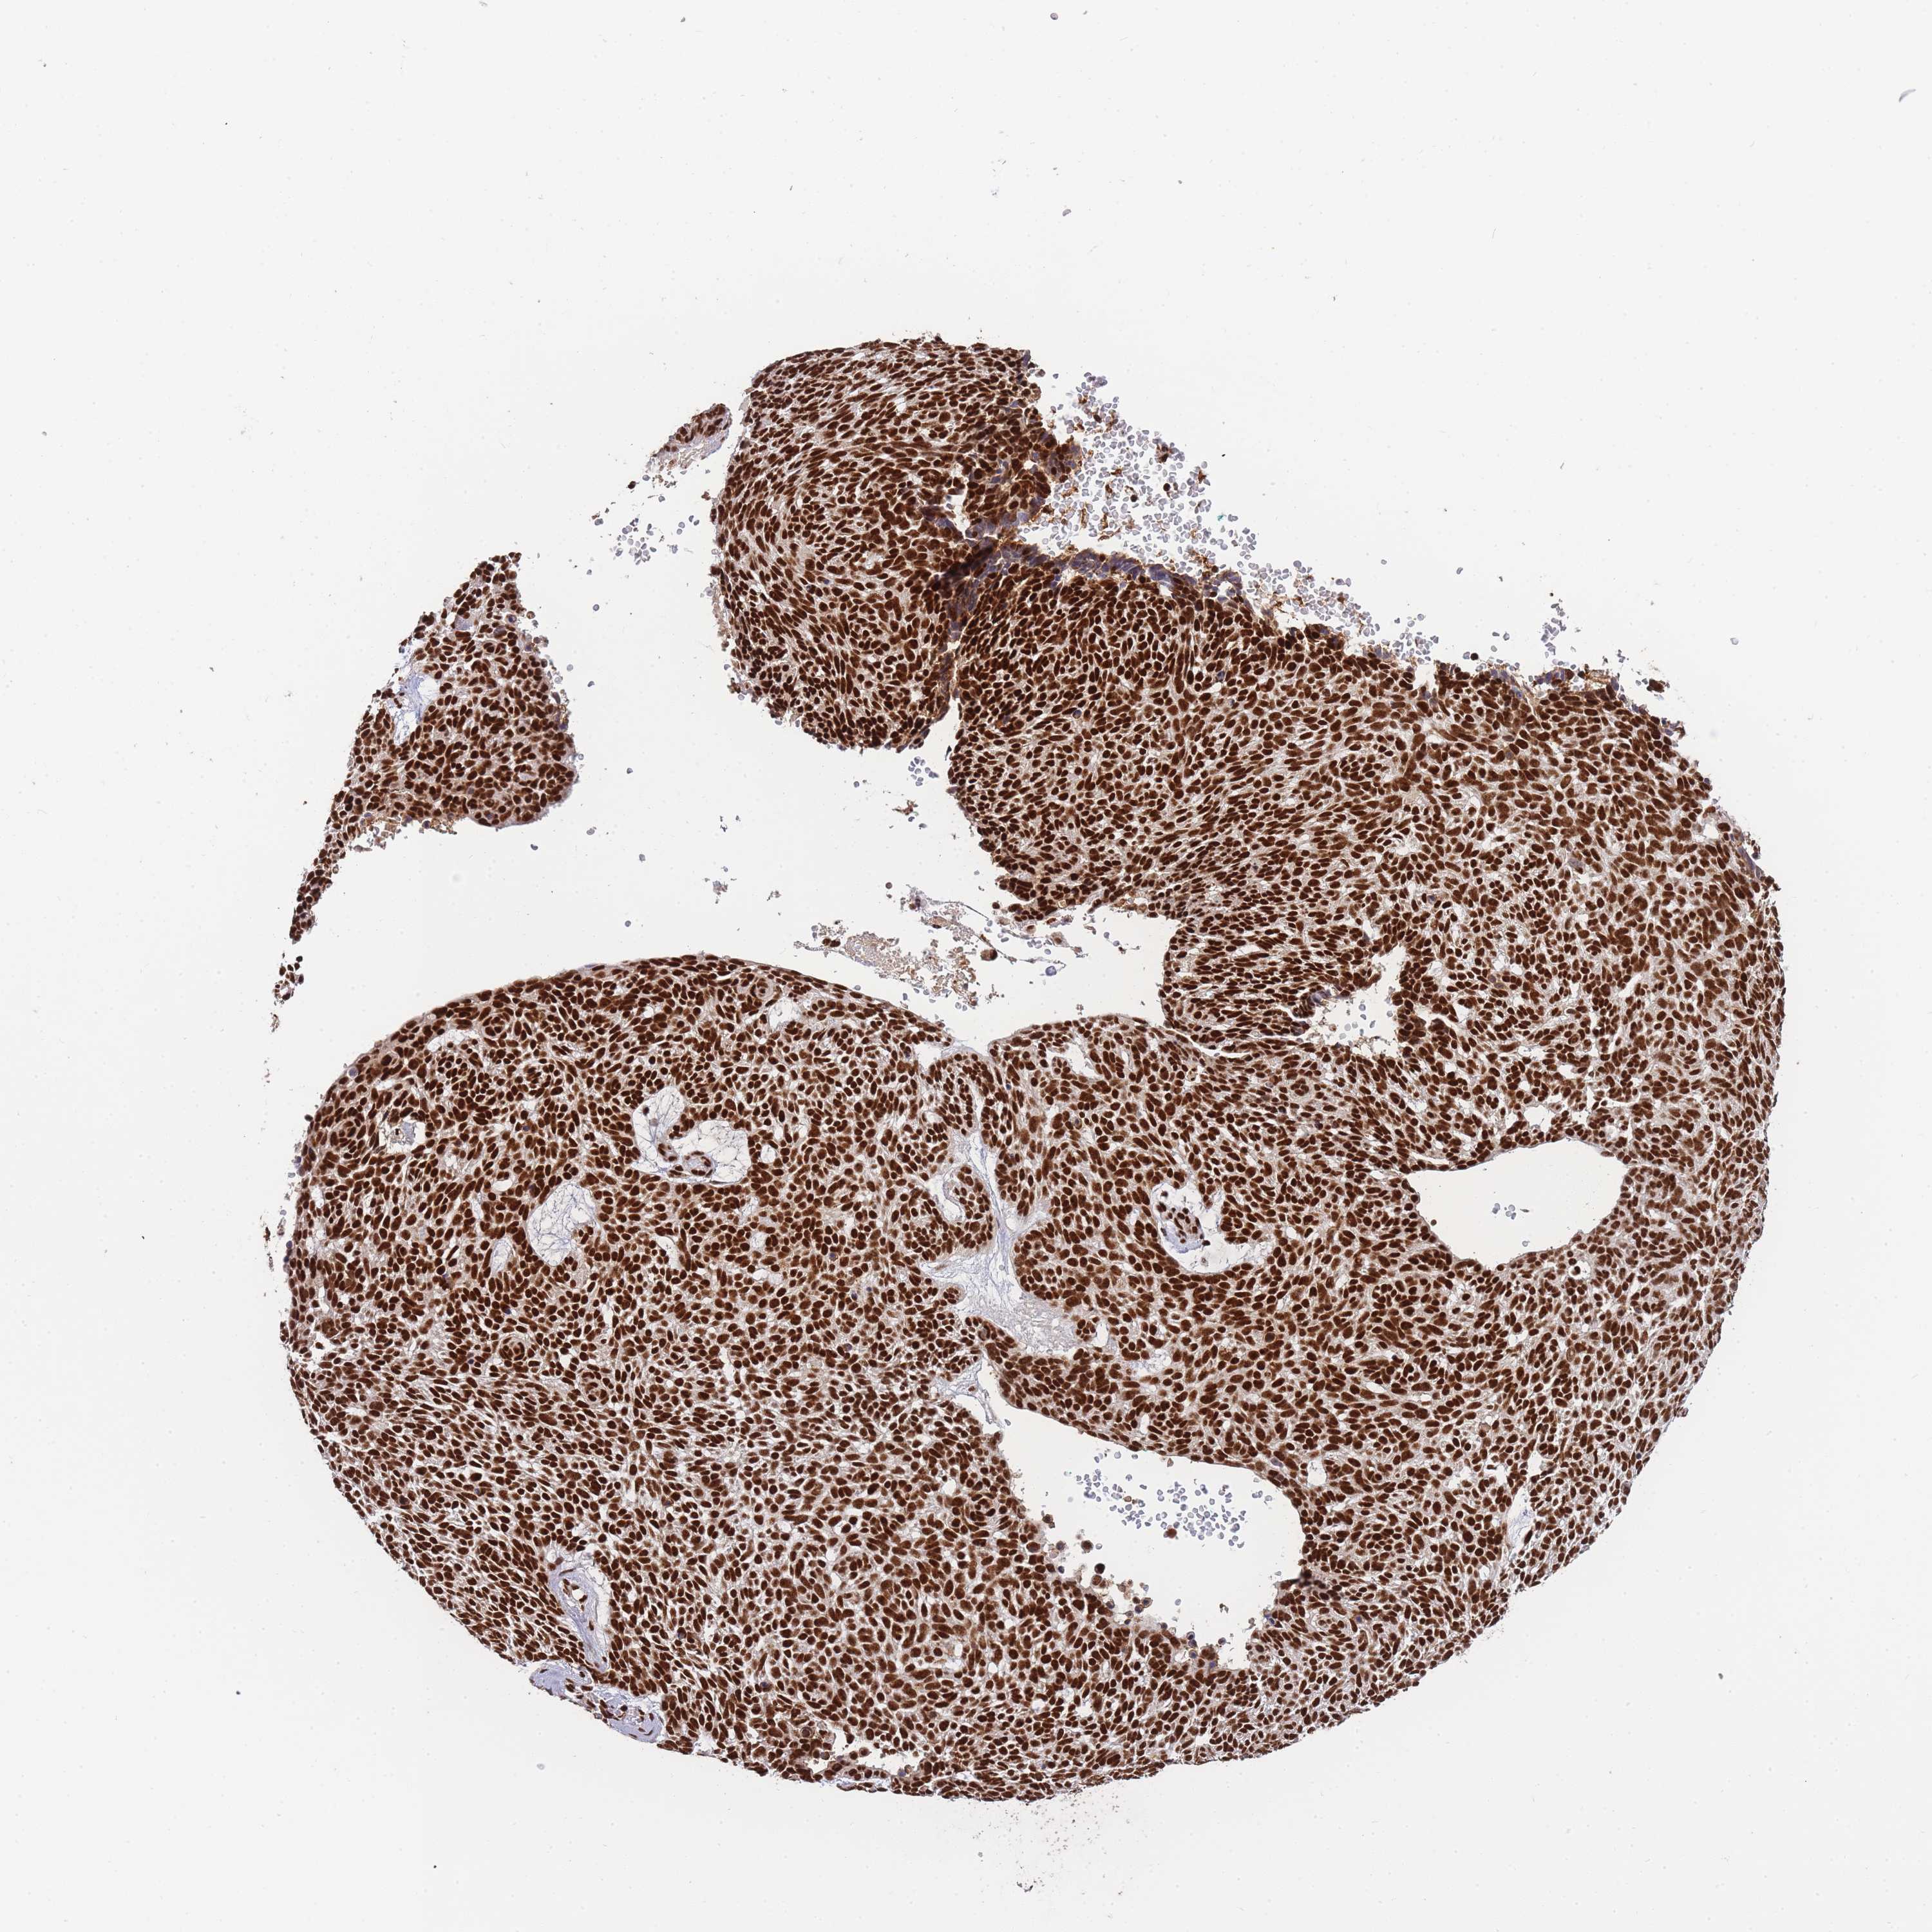

SKIN CANCER - Protein expressioni

A mouse-over function shows sample information and annotation data. Click on an image to view it in a full screen mode. Samples can be filtered based on level of antibody staining by selecting one or several of the following categories: high, medium, low and not detected. The assay and annotation is described here.

Antibody stainingi

Antibody staining in the annotated cell types in the current human tissue is reported as not detected, low, medium, or high, based on conventional immunohistochemistry profiling in selected tissues. This score is based on the combination of the staining intensity and fraction of stained cells.

Each image is clickable and will lead to virtual microscopy that enables deeper exploration of all samples and also displays staining intensity scores, fraction scores and subcellular localization as well as patient and tissue information for each sample.

Antibody HPA035174

Antibody CAB005167

Staining

High

Strong

Quantity

Location

Basal cell carcinoma